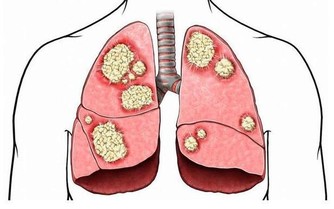

人每天進行呼吸,通過呼吸攝取氧氣,而氧氣必須抵達身體各個角落才能發揮其用處。而氧氣運輸至各個地方,這就離不開血管,需要血管來做“載體”,承載著氧氣及各類營養物質,一直傳送到各個器官內臟,從而促進身體各項機能的正常作用,以此來構建一個健康的身體。

如果血管發生堵塞,或者血管異常窄,那麼氧氣的運輸以及物質循環就會被影響,甚至受到阻礙,那麼身體需要氧氣的各個器官組織也會出現異常,功能不能正常實現,身體的健康受到危害,嚴重的話會引發更多的心腦血管疾病,危及生命。

結語:血管是人體生命安全的基礎,如果血管健康,那麼人的生命就能得到很大的保障。尤其是對於一些中老年人來說,更是要注重血管的健康問題,因為隨著年齡增加血管也會老化。